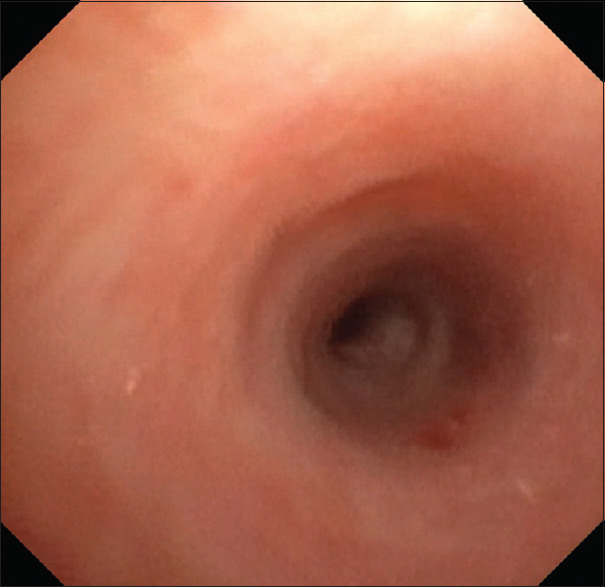

This is a case of a 3-year-old child who presented with long-segment tracheal stenosis (LSTS) and complex congenital cardiovascular disease for surgical intervention. The ideal operation for this child will include slide tracheoplasty and multiple cardiac lesion repairs. However, the low birth weight and extremely young age present a dilemma as to whether to perform total repair simultaneously or in stages. Age and weight by which the first surgical procedure was done, cardiovascular abnormality details, preoperative respiratory support, preoperative tracheobronchomalacia, cardiopulmonary bypass, the complexity of the surgery, and preoperative extracorporeal membrane oxygenation support are known to be predictive factors of long-term outcomes. Comparative studies between simultaneous and staged operations have shown that it is best to manage children with LSTS and complex cardiovascular anomalies in stages.

Abstract Image